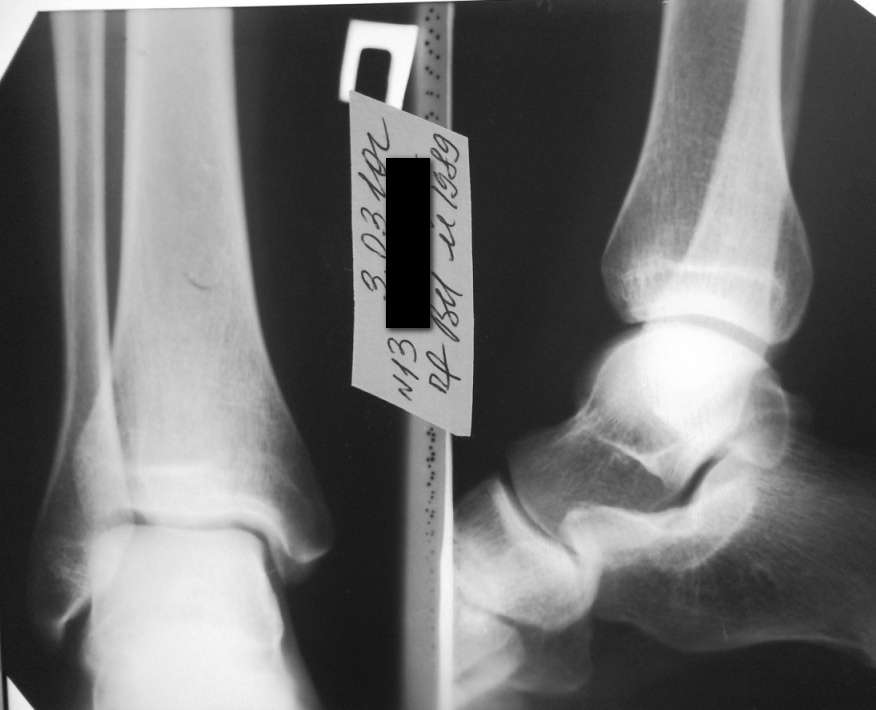

Здравствуйте уважаемые коллеги! Больной 1989 г.р. Беспокоит боль в области нижней трети правой голени.

с медиальной стороны, при ходьбе и пальпации надкостнецы большеберцовой кости, по переднемедиальной поверхности от лодыжки до граници нижней и средней трети. Более в течении недели, начало постепенное, без видимых причин. Травму отрицает. Визуально никаких изменений нет ни в объеме конечности, ни во внешнем виде кожных покровов. Боль только при нагрузке, в покое и ночью не болит. Заранее благодарю за высказанные мнения по поводу диагноза. Снимки прилагаю.

Спасибо за ответ Дмитрий. Периостит я рассматривал, но смущало отсутствие предпосылок. Больной не занимается спортом, нет физических перегрузок. По снимку я ничего не обнаружил и по этому потому попросил помощи.